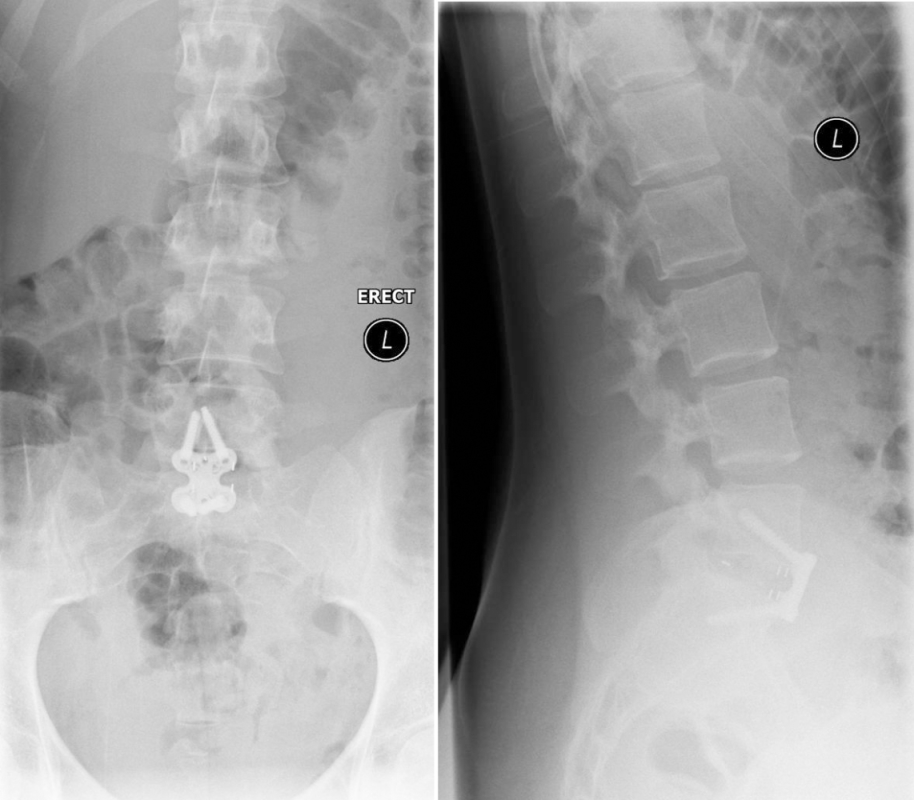

The preoperative standing image of the lumbar spine revealed a flat back with no obvious degeneration of the adjacent segment L1/L2 (Fig 6ab). The implants seemed regularly placed. After wide laminectomy, the spinal canal was open over the whole lumbar spine, illustrated on the MRI scan (Fig 6c).

From six months postoperatively, leg discomfort decreased. Within an additional four months, pain disappeared completely and both foot and hip weakness recovered. The back pain persists to a certain extent but is not impedingthe patient in her daily activities. The x-ray taken 10 months after the anterior revision surgery revealed a complete and solid fusion on both levels (Fig 8). This is confirmed by the appearance of dense bone in the radiolucentcage.